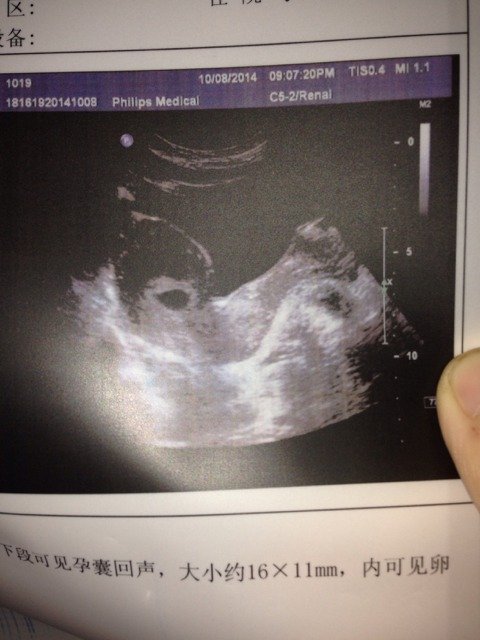

b超图,这是双胞胎嘛? 做b超时,医生说有两个孕囊,可是单子上没写。单子打印的也没有在机器上看的清楚。

你好,看你提供的检查的报告单上是应该孕囊的回事啊,而且图片上夜是一个孕囊的回声的,应该是一个的,